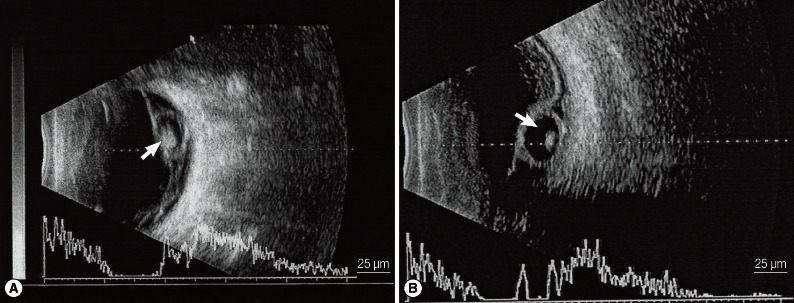

B ultrasonography revealed a round or oval vesicle-like echogenic mass in the vitreous chamber and a low-level echogenic mass in the vesicle, which indicated that the high-level echogenic spot was the scolex of the cysticercus (Fig. 2A). Through retinal detachment, a high-level echo in the membrane connected to the optic nerve as well as masses of varying echo levels caused by intravitreous bleeding and exudation were detected. For subretinal cysticercus, a strip echo connected to the optic nerve anterior to the cysticercus was detected (Fig. 2B).

Fig. 2

A) A cysticercus in the vitreous body shown by B ultrasonography. A round or oval vesicle-like echogenic mass can be seen in the vitreous body, and the high-level echo spot in it is the scolex (white arrow). B) A cysticercus in the subretinal region shown by B ultrasonography. An echo strip connected to the optic nerve is found anterior to the cysticercus (white arrow).